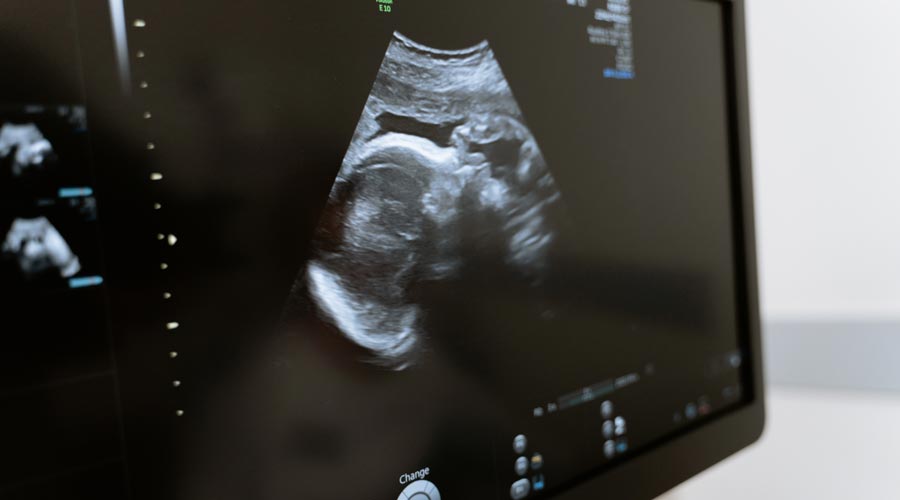

Wenn du und dein Partner gesund seid, steht eurem Kinderwunsch nichts im Wege. Zur Sicherheit könnt ihr vorab einige Checks durchführen lassen: Eine Ultraschalluntersuchung bei deiner Frauenärztin kann überprüfen, ob deine Eierstöcke richtig funktionieren. Eine Spermienanalyse beim Urologen zeigt, wie zeugungsfähig dein Partner ist. Vor allem aber: Entspannt euch! Besonders nach langer Pilleneinnahme kann es einige Zyklen dauern, bis sich dein Körper wieder umstellt.